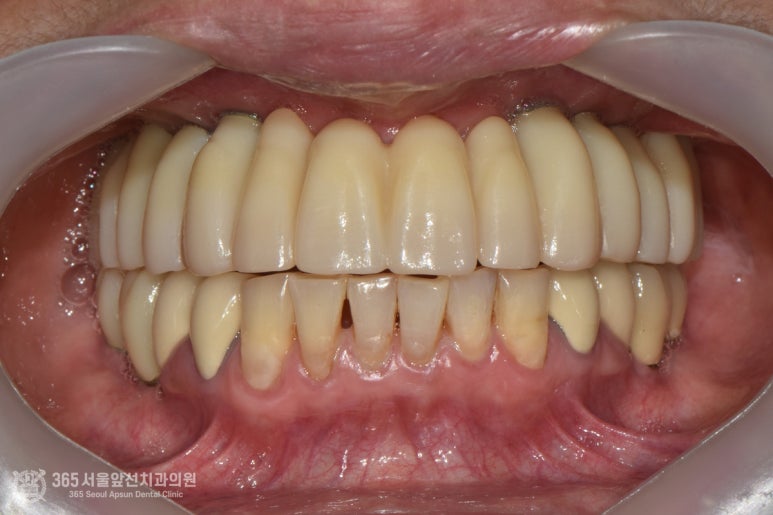

촬영일시: 2024.06.07. 처음 오셨을때 엑스레이 사진입니다. 윗턱과 아래턱 모두 뼈가 매우 적은편입니다. 특히 윗턱의 앞니쪽은 뼈가 고작 3mm밖에 존재하지 않았습니다. 매우 난증례에 해당한다고 볼 수 있겠습니다. 앞니 부위 뼈가 매우 부족하고(3mm) 어금니쪽도 전체적으로 뼈가 매우 적었습니다. 앞니와 어금니의 부족한 뼈를 만들어내면서 임플란트 식립을 계획했습니다. 통상적으로 윗턱에서 뼈가 부족할때 사용하는 수술방법으로 상악동거상술이라는 잘 알려진 술식이있는데요. 상기 환자분의 경우, 앞니쪽까지도 뼈가 부족했기에 코로 접근해서 부족한 뼈를 만들어 내는 비강거상술까지 동반하여 임플란트 수술을 진행했습니다. 촬영일시: 2024.08.10. 좌우측 상악동 거상과 비강거상을 동반하여 윗턱에 임플란트 8개를 식립했습니다. 지금까지 만나뵈었던 많은 환자분들 중 뼈의 상태가 매우 안좋은 편에 속하셨으며 매우 난해한 증례였습니다. 그렇지만 수술은 성공적으로 잘 마무리되었습니다. 위아래 전체 임플란트를 식립한 후 엑스레이 사진입니다. 임플란트가 가지런히 잘 배열되어있습니다 ㅎㅎ 지르코니아라는 재료를 사용하여 치아색상으로 단단하게 보철물도 제작했습니다. 촬영일시: 2024.12.29. 최종적으로 마무리된 엑스레이 사진입니다. 촬영일시: 2024.12.29. -노란색: 원래 환자분의 윗턱뼈 -주황색: 상악동거상술을 통해 만들어진 뼈 -보라색: 비강거상술을 통해 만들어진 뼈 최종적으로 치료가 완료된 후 구강내 사진입니다.

촬영일시: 2024.12.29. 워낙에 뼈가 없으셨던 환자분이셔서 치아가 다소 긴 형태로 제작될 수 밖에 없다는 것은 한계점이긴합니다만, 환자분께서는 틀니가 아니라 임플란트를 이용하여 치료를 받으신 것에 매우 만족하셨던 증례입니다. "틀니를 벗으니 세상 행복하네요. 고맙습니다." 환자분께서 치료를 마치시고 제게 한 첫마디입니다. 이런 기분에 치과의사를 하게되는 것 같습니다. 오늘은 제게 매우 특별한 증례를 소개해드렸습니다 ㅎㅎ 대부분의 환자분들은 상기 환자분의 증례에 비하면 난이도가 매우 낮으니 너무 걱정하지 않으셔도 괜찮을 것 같습니다. 앞으로도 좋은 증례로 찾아뵙겠습니다. 미추홀구치과 365서울앞선치과의원이었습니다. 감사합니다. ※ 365서울앞선치과의원의 모든 포스팅은 각 진료과 의료진이 직접 작성합니다. 365서울앞선치과의원 블로그의 임상 케이스 게시물은 환자분께 의학적으로 정확하고 상세한 정보를 드리기 위해 각 진료과 의료진이 직접 작성하며, 모든 증례 사진은 본원 의료진이 직접 시술한 증례를 촬영한 것으로, 의료법 제23조, 제56조에 의거하며 환자분의 동의를 얻어 포스팅에 사용하였습니다. 또한 해당 케이스는 본 환자분의 치료 결과이며, 환자 상태에 따라 치료의 결과는 달라질 수 있습니다. |